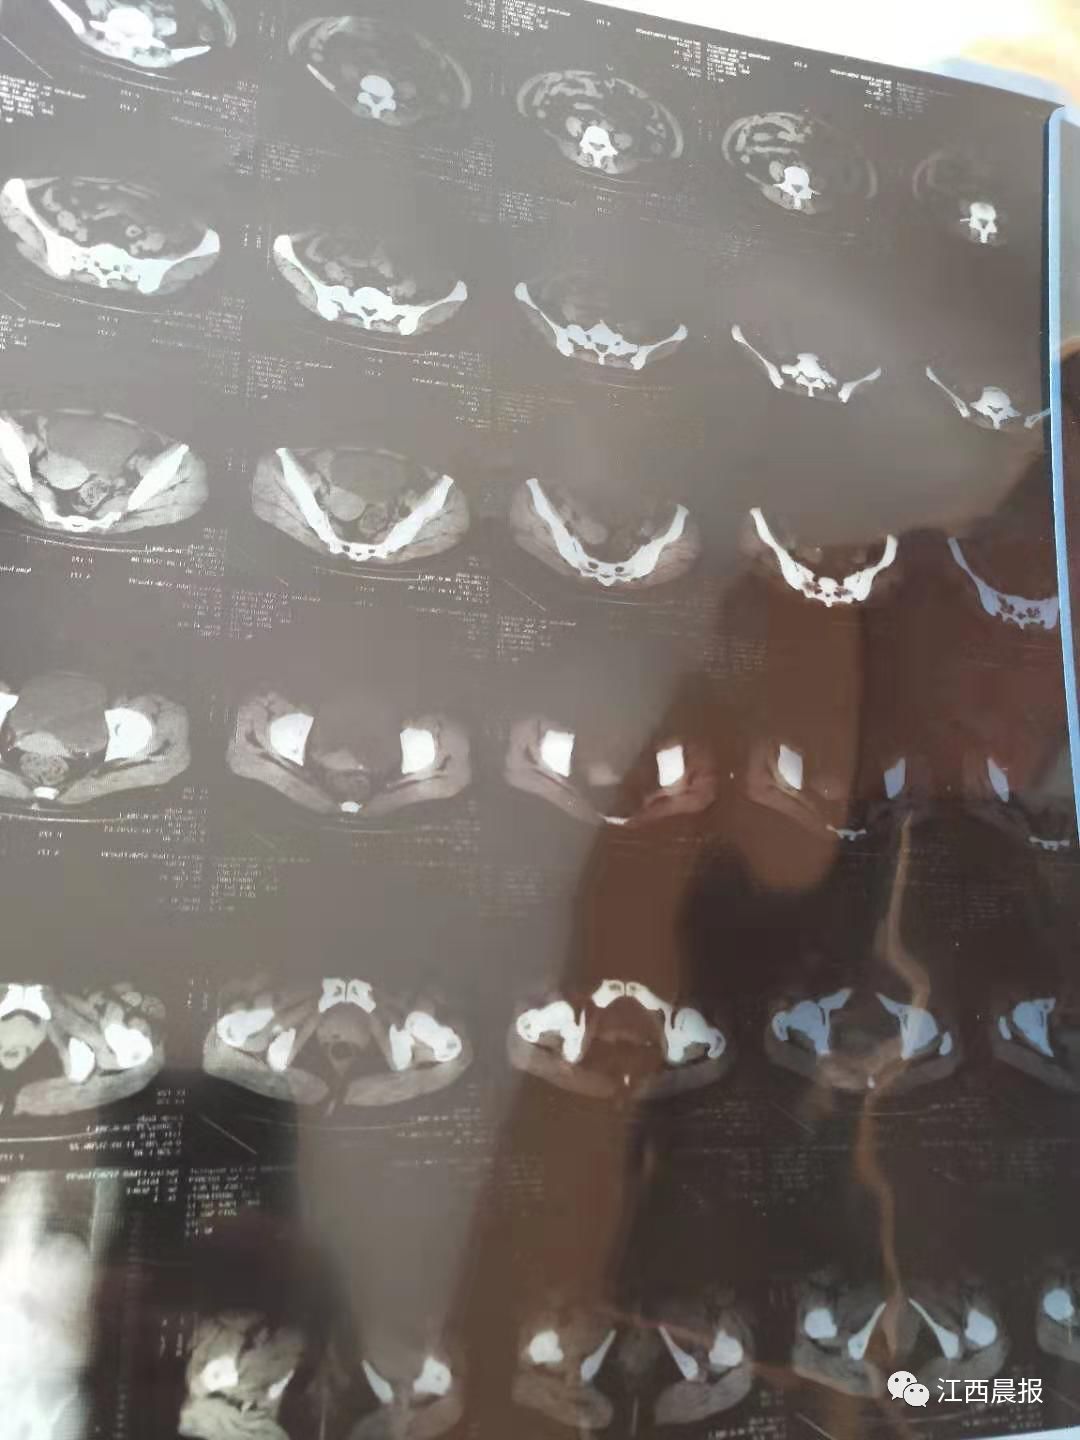

另一张11月14日的CT诊断报告则显示,张先生的母亲左肾仍有结石,且最大的达到0.9cm*0.5cm。